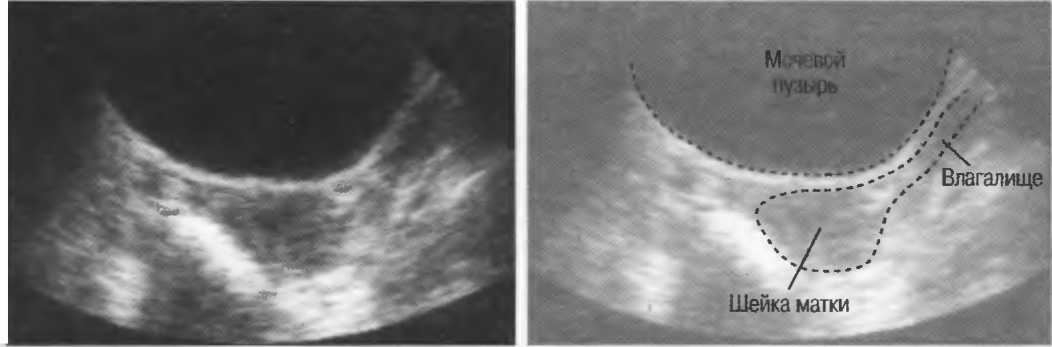

Акустическое окно |

Ткань или структура, не препятствующая распространению ультразвуковых волн и таким образом являющаяся окном для визуализации более глубоко расположенных структур. Например, заполненный жидкостью мочевой пузырь создает великолепное акустическое окно, через которое происходит визуализация тазовых структур. Обычно правую почку легче визуализировать через печень, чем через толстые мышцы спины. В этом случае печень является акустическим окном. |

Ткани очень отличаются по характеру их взаимодействия с ультразвуком. Например, кости скелета и газ в кишечнике или легких значительно отличаются от мягких тканей. Когда ультразвуковые волны встречают на своем пути кость или газ, они в большей степени отражаются или преломляются. Поэтому практически невозможно эффективно использовать ультразвук при наличии большого количества газа в кишечнике: при исследовании малого таза необходимо как можно полнее наполнять мочевой пузырь для того, чтобы приподнять кишечник и убрать его с пути прохождения ультразвуковых волн. Из-за наличия воздуха практически невозможно исследовать легкие, однако можно визуализировать жидкость в плевральной полости или опухоль, соприкасающуюся со стенкой грудной полости.